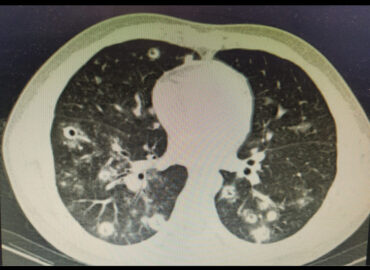

Paciente masculino de 21 años, oriundo de Corrientes Trabajador en tambo APP: covid + 12/2022 alta epidemiológica. No vacunado […]